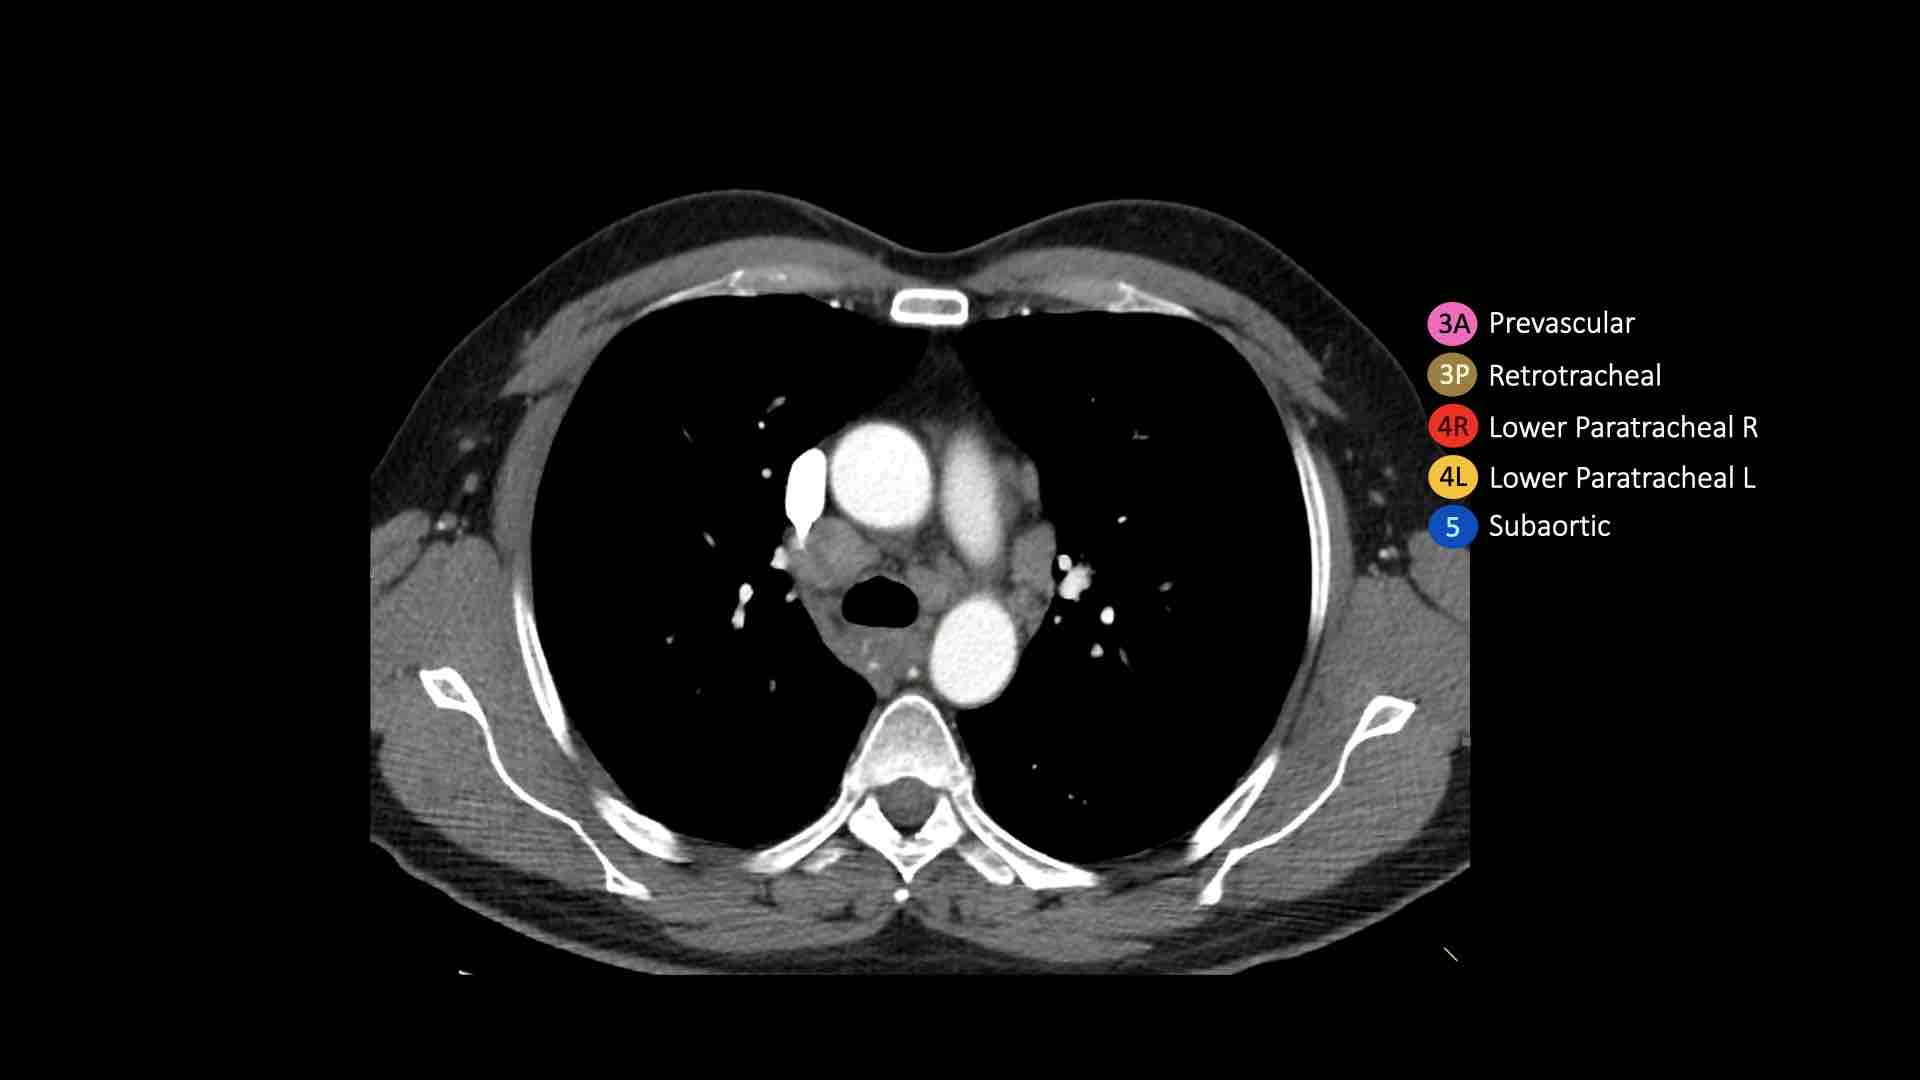

3A.Trước mạch máu

Các hạch này không tiếp giáp với khí quản như các hạch ở nhóm 2, mà nằm ở phía trước các mạch máu.

3P.Trước cột sống

Các hạch không tiếp giáp với khí quản như các hạch ở nhóm 2, mà nằm sau thực quản, tức là ở vị trí trước cột sống.

4R.Cạnh khí quản dưới

Từ điểm giao nhau giữa bờ dưới tĩnh mạch vô danh (tĩnh mạch tay đầu trái) với khí quản đến bờ dưới tĩnh mạch đơn.

Hạch nhóm 4R trải dài từ bờ bên phải đến bờ bên trái của khí quản.

4L.Cạnh khí quản dưới

Từ bờ trên của quai động mạch chủ đến bờ trên của động mạch phổi trái.

5. Dưới động mạch chủ

Các hạch này nằm trong cửa sổ phế động mạch (AP window), ở phía ngoài dây chằng động mạch.

Các hạch này không nằm giữa động mạch chủ và thân động mạch phổi mà nằm ở phía ngoài các mạch máu này.

Bên trái là hình ảnh ngay trên mức thân động mạch phổi, cho thấy các hạch cạnh khí quản dưới bên trái và bên phải.

Ngoài ra còn có các hạch nhóm 3 và nhóm 5.

Bên trái là hình ảnh ở mức phần dưới khí quản, ngay trên carina.

Bên trái khí quản là các hạch 4L.

Lưu ý rằng các hạch 4L này nằm giữa thân động mạch phổi và động mạch chủ, nhưng không nằm trong cửa sổ phế động mạch, vì chúng nằm ở phía trong dây chằng động mạch.

Hạch nằm bên ngoài thân động mạch phổi là hạch nhóm 5.